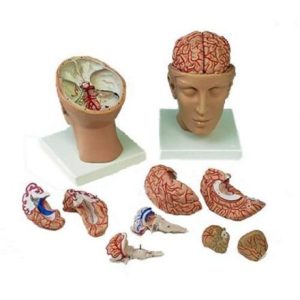

مولاژ کلمه ای فرانسوی به معنای قالب است. آناتومی بدن انسان با تجهیزاتی مانند مولاژهای پزشکی یا کالبدشناسی که نمونه هایی تخصصی و شبیه به اندام های بدن انسان هستند، به دانش آموزان و دانشجویان آموزش داده می شود. استفاده از مولاژ در روند یادگیری و آموزش تاثیر به سزایی داشته و تمامی اندام ها را با تمامی جزئیات و با کیفیت بالا می توان مشاهده و بررسی کرد. مولاژها عموما از جنس PVC نشکن، لاستیک یا فوم ساخته شده و دارای رنگ طبیعی و قابل شست و شو هستند. برخی از انواع مولاژها مناسب برای آموزش مراقبت های پزشکی و پرستاری است و امکان تمرین بانداژ، تزریق، CPR، جراحی و... وجود دارد. مولاژها معمولا هر کدام عضوی از بدن را نمایش می دهند و قابلیت تفکیک و مشاهده همه بخش های آن وجود دارد.

مولاژها معمولا با توجه به نوع اعضا و یا دستگاه های بدن در اندازه طبیعی، کوچکتر و یا چندین برابر بزرگتر ساخته می شوند تا امکان مشاهده دقیق اجزای آن ها فراهم شود. برخی مولاژها از چندین قطعه ساخته شده اند که قابلیت تفکیک دارند. علاوه بر نمایش ساختار و نحوه عملکرد اعضای بدن، ماهیچه ها و عضلات بدن را نیز می توان به کمک مولاژها مشاهده کرد.